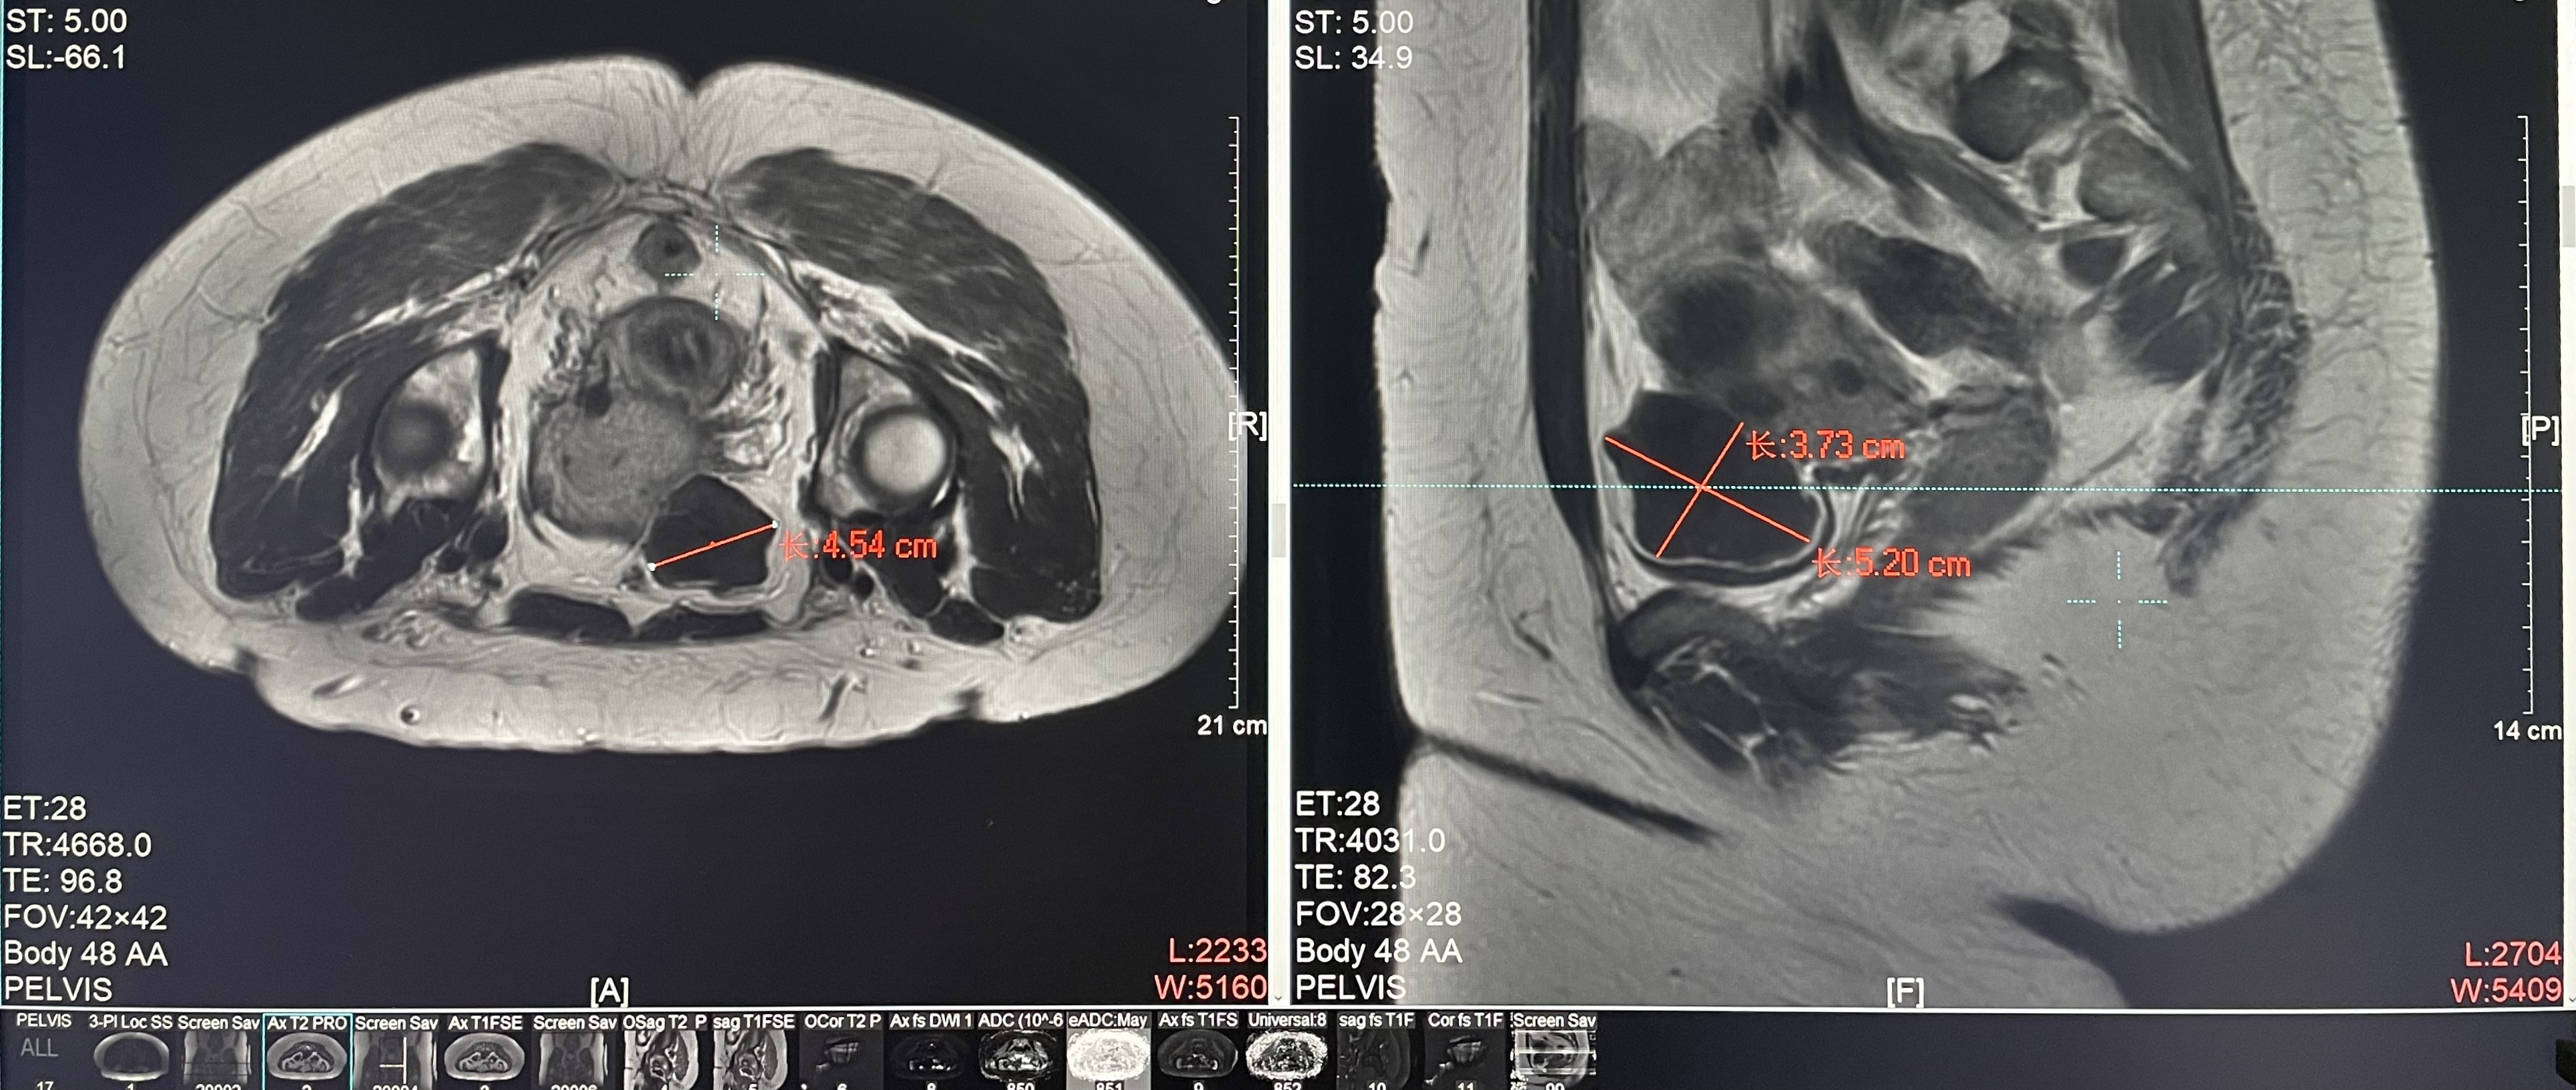

Uterine fibroids

Patient Information:Female,38

Diagnosis: Uterine fibroids

Tumor size: about 45*52*38mm

Postoperative evaluation: Postoperative enhanced imaging showed a good overlap between the ablation area (right) and the tumor area (left), the non-perfusion area was continuous and consistent.

Conclusion:It has a excellent ablation effect on this tumor, and the temperature rise curve during treatment is in line with expectations. The 240CEM area of each treated target is large, full and continuous.The ablation effect was very good,the NPV volume ratio was about 70%.